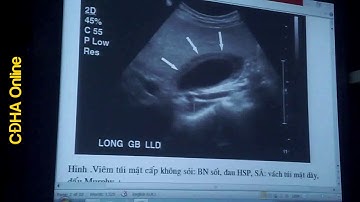

Siêu âm bụng cấp cứu - BS. Nguyễn Cao Cương